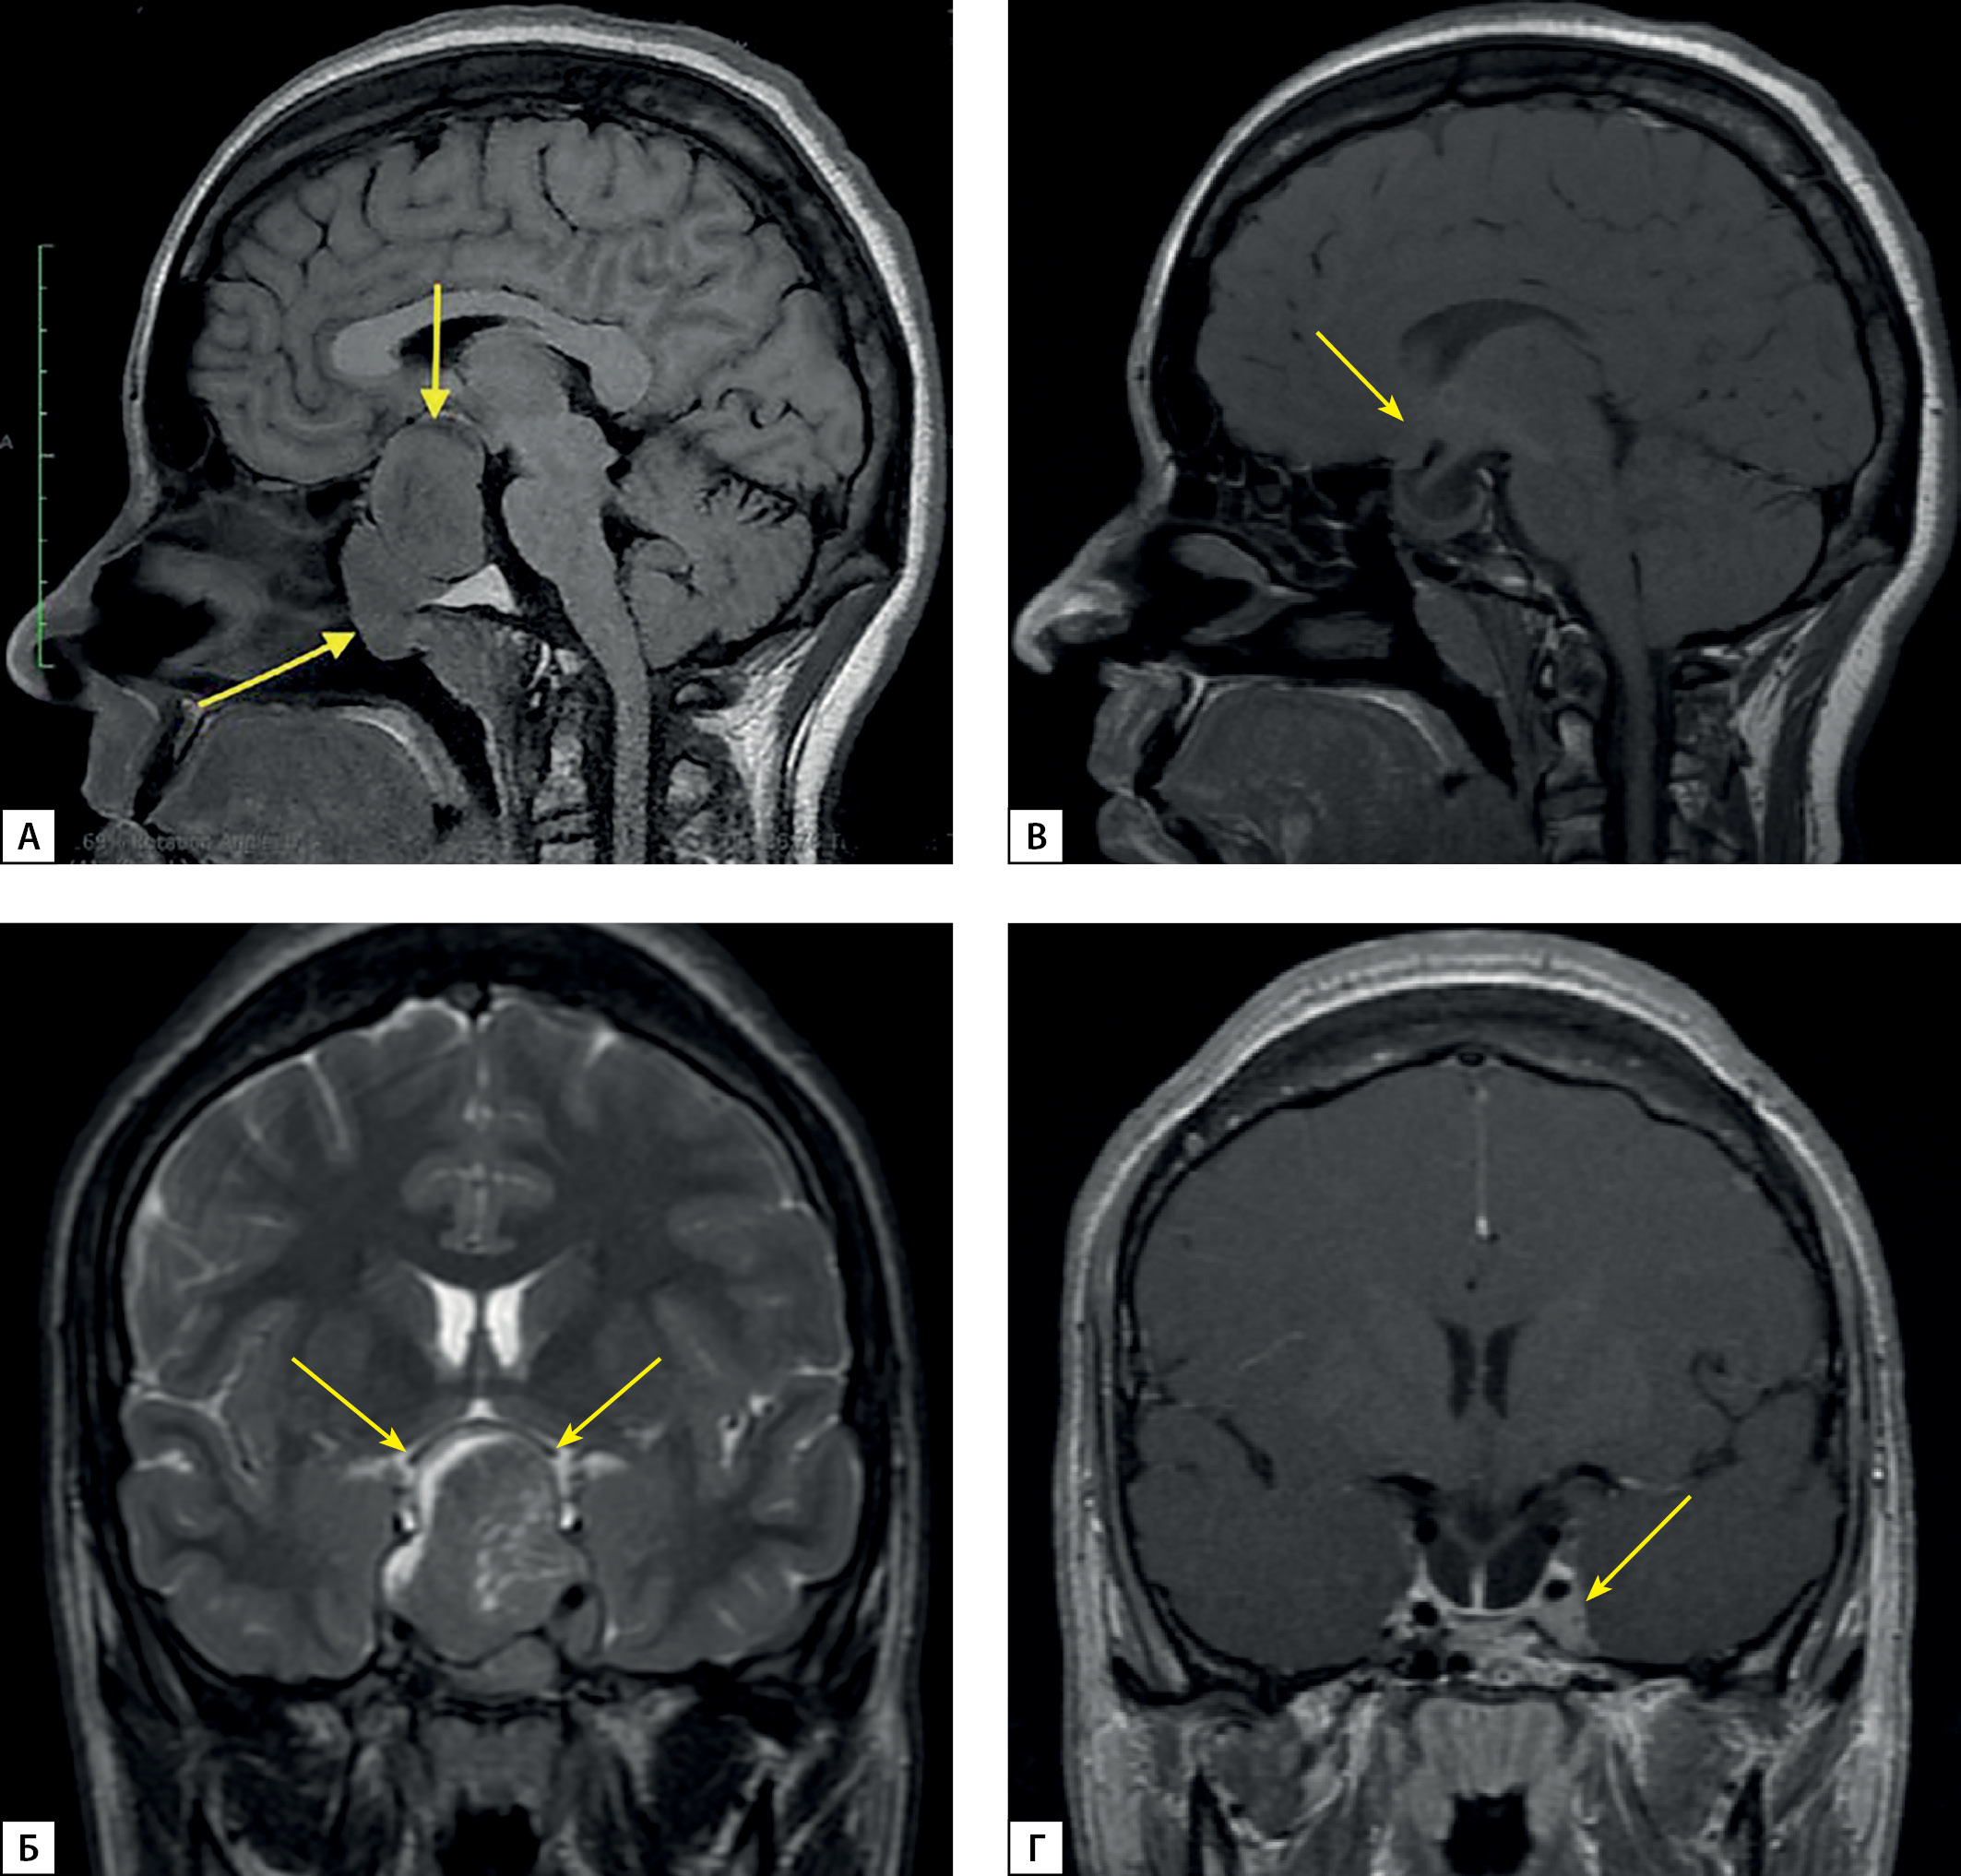

Выполнена магнитно-резонансная томография (МРТ) головного мозга, которая позволила визуализировать кистозно-солидное образование — аденому гипофиза больших размеров, 57×35×32 мм, локализованную в полости турецкого седла и распространяющуюся в область супраселлярной цистерны, в пазуху клиновидной кости и кавернозные синусы (рис. 1). Кроме этого, отмечена инвазия образования в область верхушки правой орбиты, задние ячейки решетчатой кости справа и носоглотку, с сужением ее просвета на одну треть. Аденома смещала и компримировала перекрест зрительных нервов, воронка и задняя доля гипофиза не дифференцировались. Степень инвазии аденомы соответствовала III(D), IV(S) степени в соответствии со шкалой Knosp.

Рисунок 2. МРТ головного мозга с внутривенным контрастированием

А, Б — макроаденома гипофиза до операции. Сагиттальная и фронтальная проекции соответственно; В, Г — Послеоперационные изменения, остаточная ткань аденомы. Сагиттальная и фронтальная проекции соответственно.